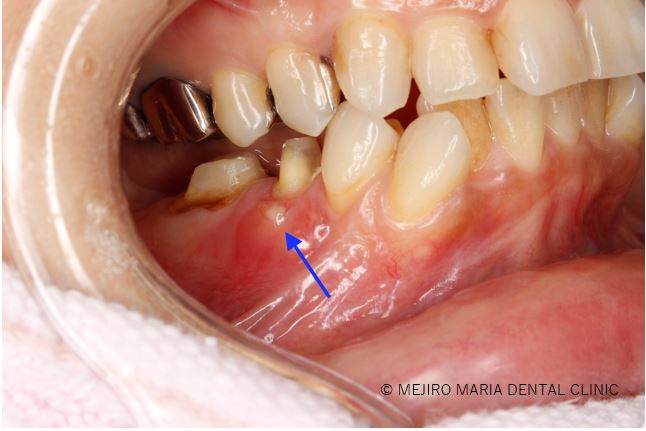

手術を開始したところ、右下5番根尖頬側に見逃し根管(手のつけられていない根管)を確認し、通法通り、根尖側3mmを切断し、逆根管形成後MTAにて逆根管充填を行った。

この症例は右下4番、5番に限局的な歯周ポケットを確認し、原因の歯がどこであるのかを特定するのが困難でした。 当院では右下4番の歯髄反応は正常と判断し、CT撮影などの診査の結果、右下5番6番の精密根管治療が必要であったため治療を実施しました。 しかしながら、精密根管治療終了後にも引続き瘻孔(膿の排出)が確認でき、根尖性歯周炎は治癒には至らず歯内療法外科を行う必要があると判断しました。